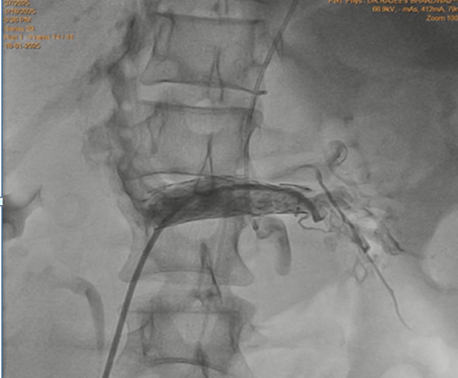

Keeping in view the possibility of Nutcracker syndrome (NKS). patient was taken up for percutaneous treatment. Right femoral vein puncture was done. Femoral vein angiography was done to see inferior vena cava (IVC), (Fig.1) to have idea of origin of left renal vein. Femoral artery access was also taken and left renal arteriography was done to trace renal vein in venous phase, but it could not be visualised. Since renal vein was not visualised, blind entry was done with terumo wire passed through right Judkins (JR)catheter. Catheter was then negotiated into LRV and venography was done (Fig. 2). It showed markedly dilated left gonadal vein (LGV), and left ovarion vein (Fig 3). Hardly any contrast was entering into IVC, due to compression by superior mesenteric artery (SMA). It was decided to put a stent in LRV across the compressed segment. To properly define the site of obstruction and stent placement, a JR catheter was placed in SMA (Fig 4), from left brachial artery approach. Self-expanding venous stent was then deployed, size 14x 60 mm. (Fig 5). LRV angio was then done which showed free flow of contrast into IVC and minimal reflux into LGV (Fig. 6). If, large reflux persisted, then coiling of LGV would have been required.

Figure 2: Left renal venography shows hugely dialted gonadal vein, with very little flow into inferior vena cava (Due to renal vein compression and reflux of blood into gonadal vein)